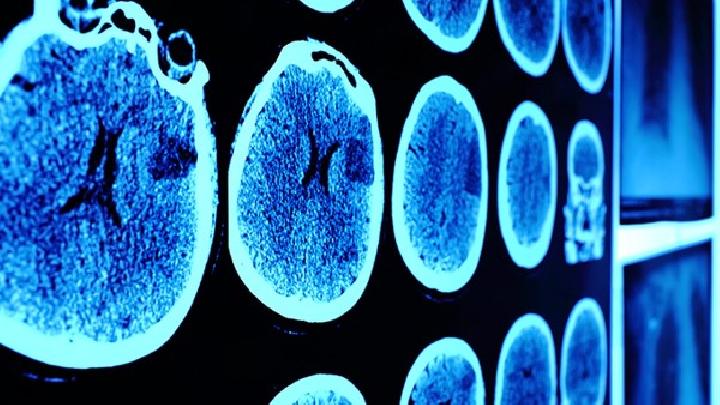

二、头CT

虽然MR脑膜瘤的诊断取代了CT之势,但是CT它仍然是诊断这种疾病的主要方法,尤其是脑膜瘤与相邻骨结构的关系和钙化。CT的表现:

1、瘤呈圆形或分叶状或扁平状,边界清晰。

2、密度均匀等或高密度,少数不均匀和低密度,伴瘤内囊变或坏死。

3.增强后密度均匀增加。

肿瘤钙化多均匀,但不规则。

5.局部颅骨可增生或损伤。

6.半数患者在肿瘤附近有不增强的低密度带,表明肿瘤周围水肿。